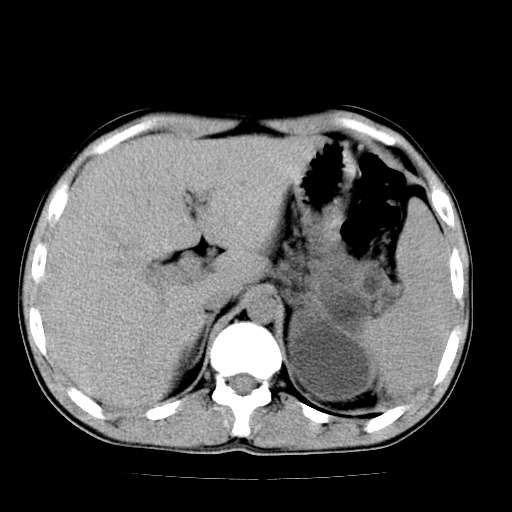

以下是引用天南地北在2007-4-30 13:36:00的发言:[br]支持慢性胰腺炎伴有假性囊肿

以下是引用andymaomao在2007-4-30 14:28:00的发言:[br]支持:1.慢性胰腺炎并假性囊肿形成可能;[br] 2.左肾形态稍增大,旋转不良。